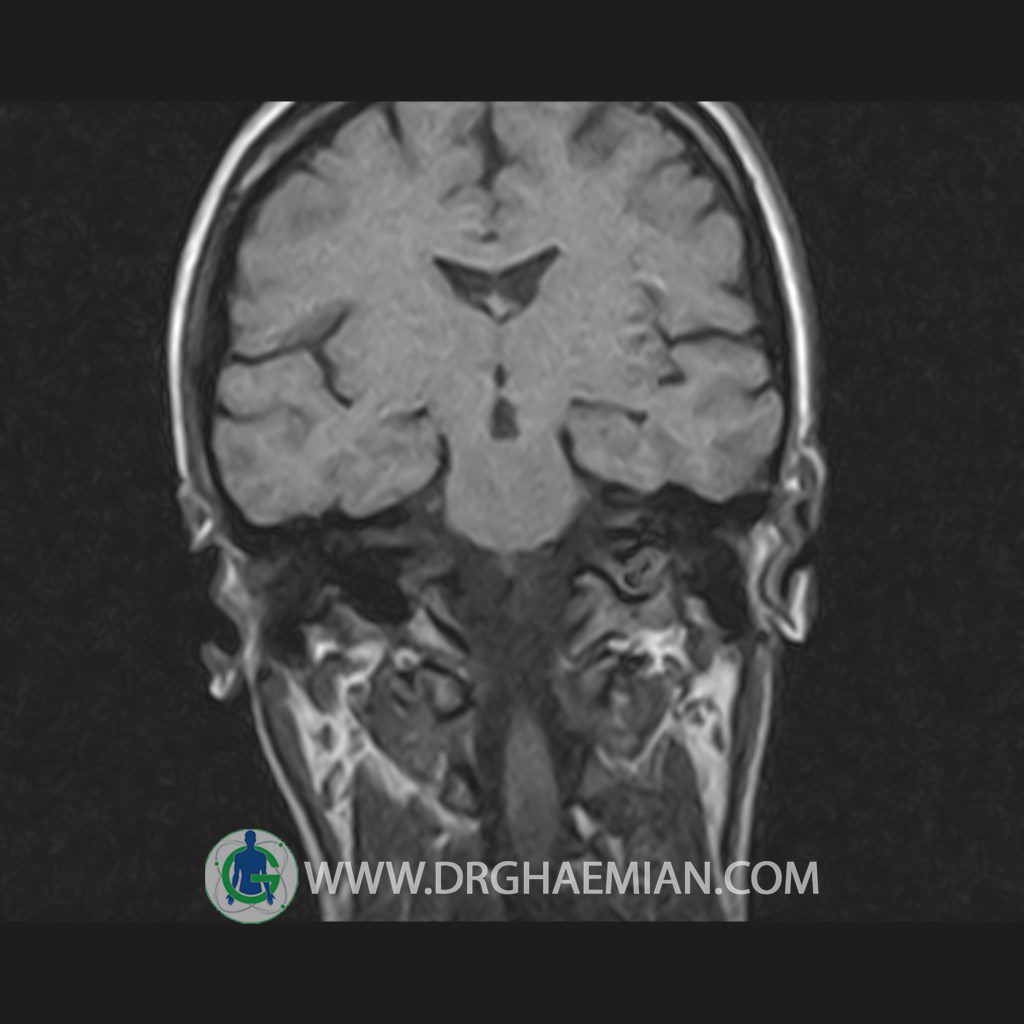

پزشکان اغلب از تصویربرداری ام آر آی برای تشخیص و درمان عارضه های پزشکی که فقط با استفاده از اشعه ایکس یا میدان مغناطیسی و امواج رادیویی قابل مشاهده است، استفاده می کنند. دستگاه ام آر آی تصاویر دقیق از ساختار های داخلی بدن ایجاد می کند. در این کیس هیپرپلازی هیپوفیز و آدنوم مشاهده می شود.

HYPOPHYSIS MRI

(with and without contrast)

Technique: Axial , coronal T1 , Axial , coronal , sagittal T2 , Axial, coronal T1 post Gd & 64 dynamic thin coronal slices.

The sella shows normal size , position and configuration .

The borders of its floor and walls are smooth and sharply defined .

The infundibulum is centered and of normal size .

The optic chiasm and suprasellar spaces appear normal .

The cavernous sinus and imaged portions of the internal carotid artery and carotid siphon are unremarkable .

Evaluable portions of the neurocranium show no abnormalities .

The sphenoid sinus is clear and pneumatized .

– Mild convexity at superior border of pituitary gland with post contrast homogeneous enhancement suggestive for pituitary hyperplasia & iso signal adenoma

is seen